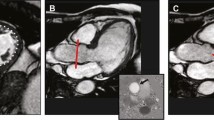

Although recent recommendations describe the numerous limitations of the 2D-PISA method, making its use difficult, one key point message remains, namely “When feasible, the PISA method is highly recommended to quantify the severity of MR” [3]. However, the exact way of measuring of the 2D-PISA radius is unclear, as illustrated in Fig. 2. In the recent guidelines [5] “The radius of PISA is measured from the point of color Doppler aliasing to the VC (vena contracta)”. However, the 2D-PISA radius is illustrated in this recommendation [5], in the first description of the method [12], and in several other references [13] from the proximal convergence area to the ostium of the regurgitant orifice. This discrepancy is not clearly analysed in the literature [5, 13,14,15]—especially using modern colour Doppler technologies. Also, the impact of MR jet orientation is being debated controversially when using the 2D-PISA method. While some recommendations advise the use of the 2D-PISA in both central and eccentric jets [3, 16], others advise caution [15].

Limitations of the 2D-PISA method (PISA radius = r)—scheme of the proximal convergence areas and the proximal regurgitant flow phenomenon through the regurgitant orifice illustrating the importance of the accurate definition of the 2D-PISA radius. Example of regurgitant volume (MVRegVol) assessment using different 2D-PISA radii with equal velocity time integrals of regurgitant velocities (r = 8 mm, MVRegVol = 19 ml; r = 11 mm, MVRegVol = 39 ml; r = 15 mm, MVRegVol = 67 ml)